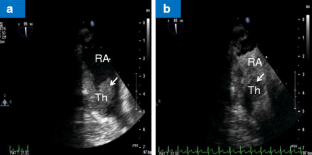

Fig. 1